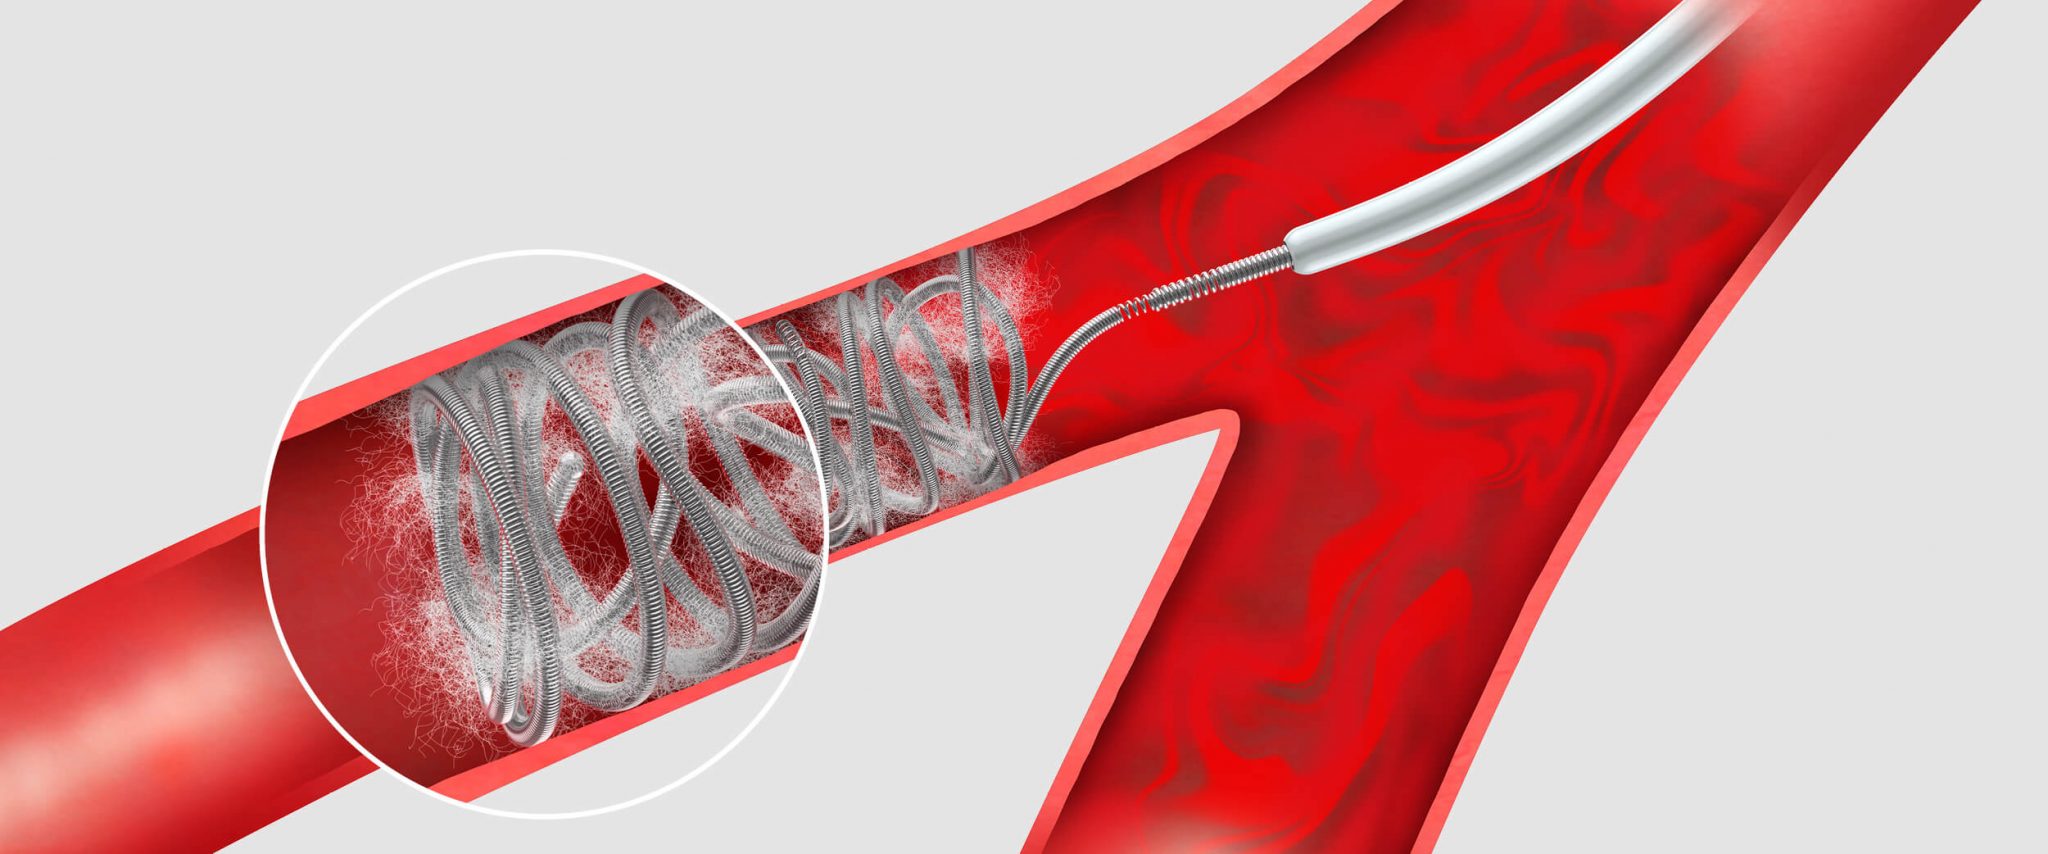

The Insight Partners recently announced the release of the market research titled Peripheral Embolization Coils Market Outlook to 2031 | Share, Size, and Growth. The report is a stop solution for companies operating in the Peripheral Embolization Coils market. The report involves details on key segments, market players, precise market revenue statistics, and a roadmap that assists companies in advancing their offerings and preparing for the upcoming decade. Listing out the opportunities in the market, this report intends to prepare businesses for the market dynamics in an estimated period.

Peripheral Embolization Coils market is all set to accommodate more companies and is foreseen to intensify market competition in coming years. Companies focus on consistent new launches and regional expansion can be outlined as dominant tactics. Peripheral Embolization Coils market giants have widespread reach which has favored them with a wide consumer base and subsequently increased their Peripheral Embolization Coils market share.

Type

- Detachable Coil

- Pushable Coil

Application

- Bleedings and Trauma

- Malformations

- Tumours

- Visceral Aneurysm

- Endoleak Type II

- Varicose Veins